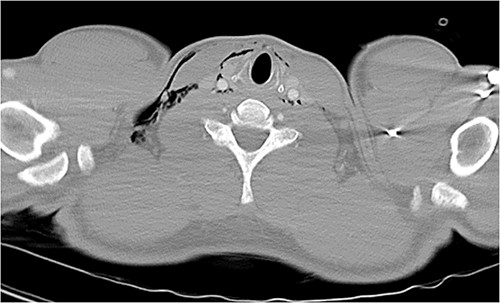

Following extubation, bilateral chest wall subcutaneous emphysema was noted extending to the neck. He also complained of central chest discomfort, without respiratory distress, oxygen desaturation or airway obstruction. Chest X-ray (CXR) revealed pneumomediastinum and surgical emphysema in the lateral chest walls bilaterally. Computed tomography (CT) of the chest, abdomen and pelvis demonstrated large volume subcutaneous emphysema bilaterally in the scrotum, abdominal and chest walls extending to the neck (see Figs 2–5). Gas was noted between the abdominal muscle layers, extraperitoneal and retroperitoneal spaces without pneumoperitoneum (see Figs 5–6). Moderate pneumomediastinum was prominent within the superior and antero-inferior mediastinum without evidence of tracheal or oesophageal injury and an associated small left pneumothorax was noted (see Figs 1–3).

CT chest and neck axial, subcutaneous emphysema extending to neck.